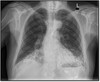

Q

What pathology is shown here? How do we know?

A

Cystic fibrosis

-Haziness inside the airway is the mucus, bronchiectasis (dilation of the airways)